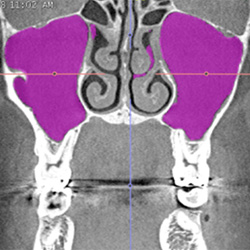

Volumenbestimmung

der Kieferhöhlen